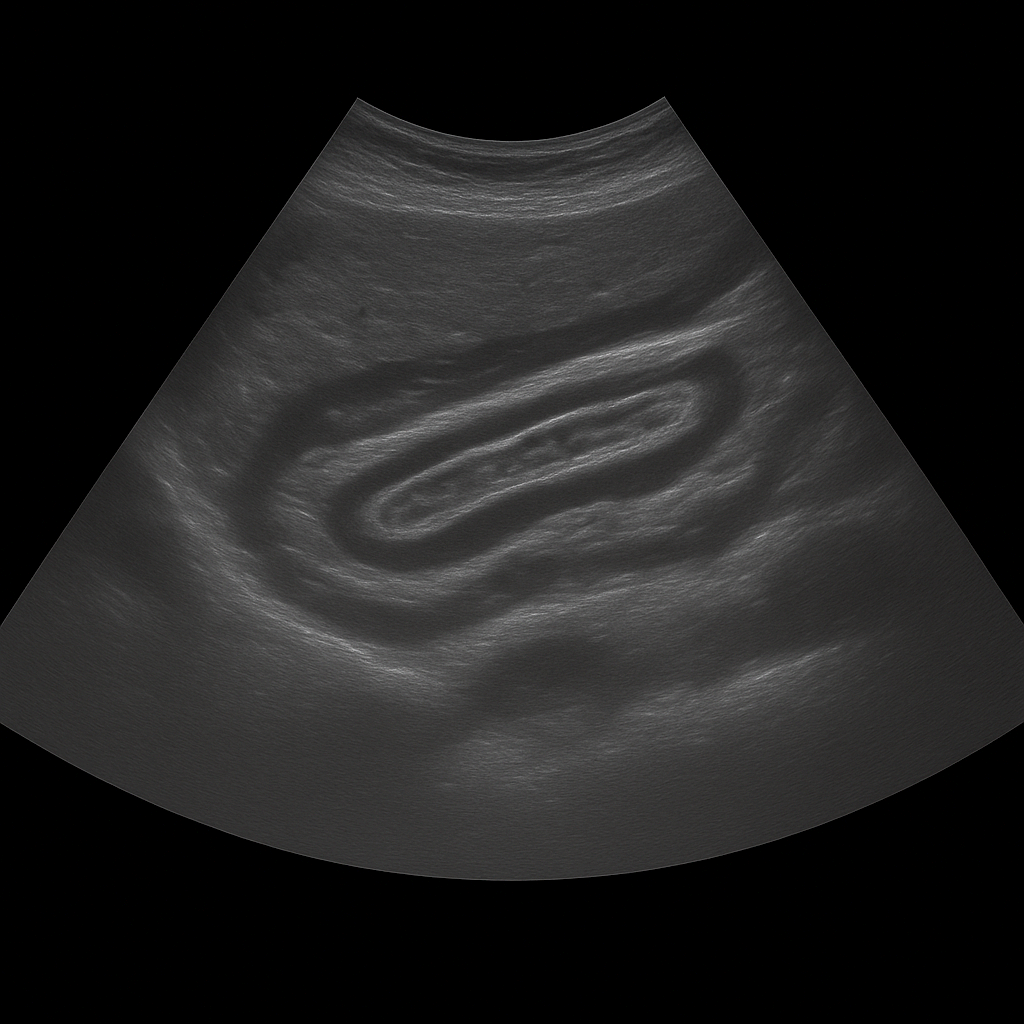

- Ultrasound of the abdominal wall shows hernias, fluid accumulations, hematomas and changes in the abdominal tissue.

- Used for pain, swelling, lumps or suspected abdominal wall hernia.

- Quick, painless and radiation-free examination of the superficial tissues of the abdomen.

- Written opinion and recommendation from a specialist doctor are included.